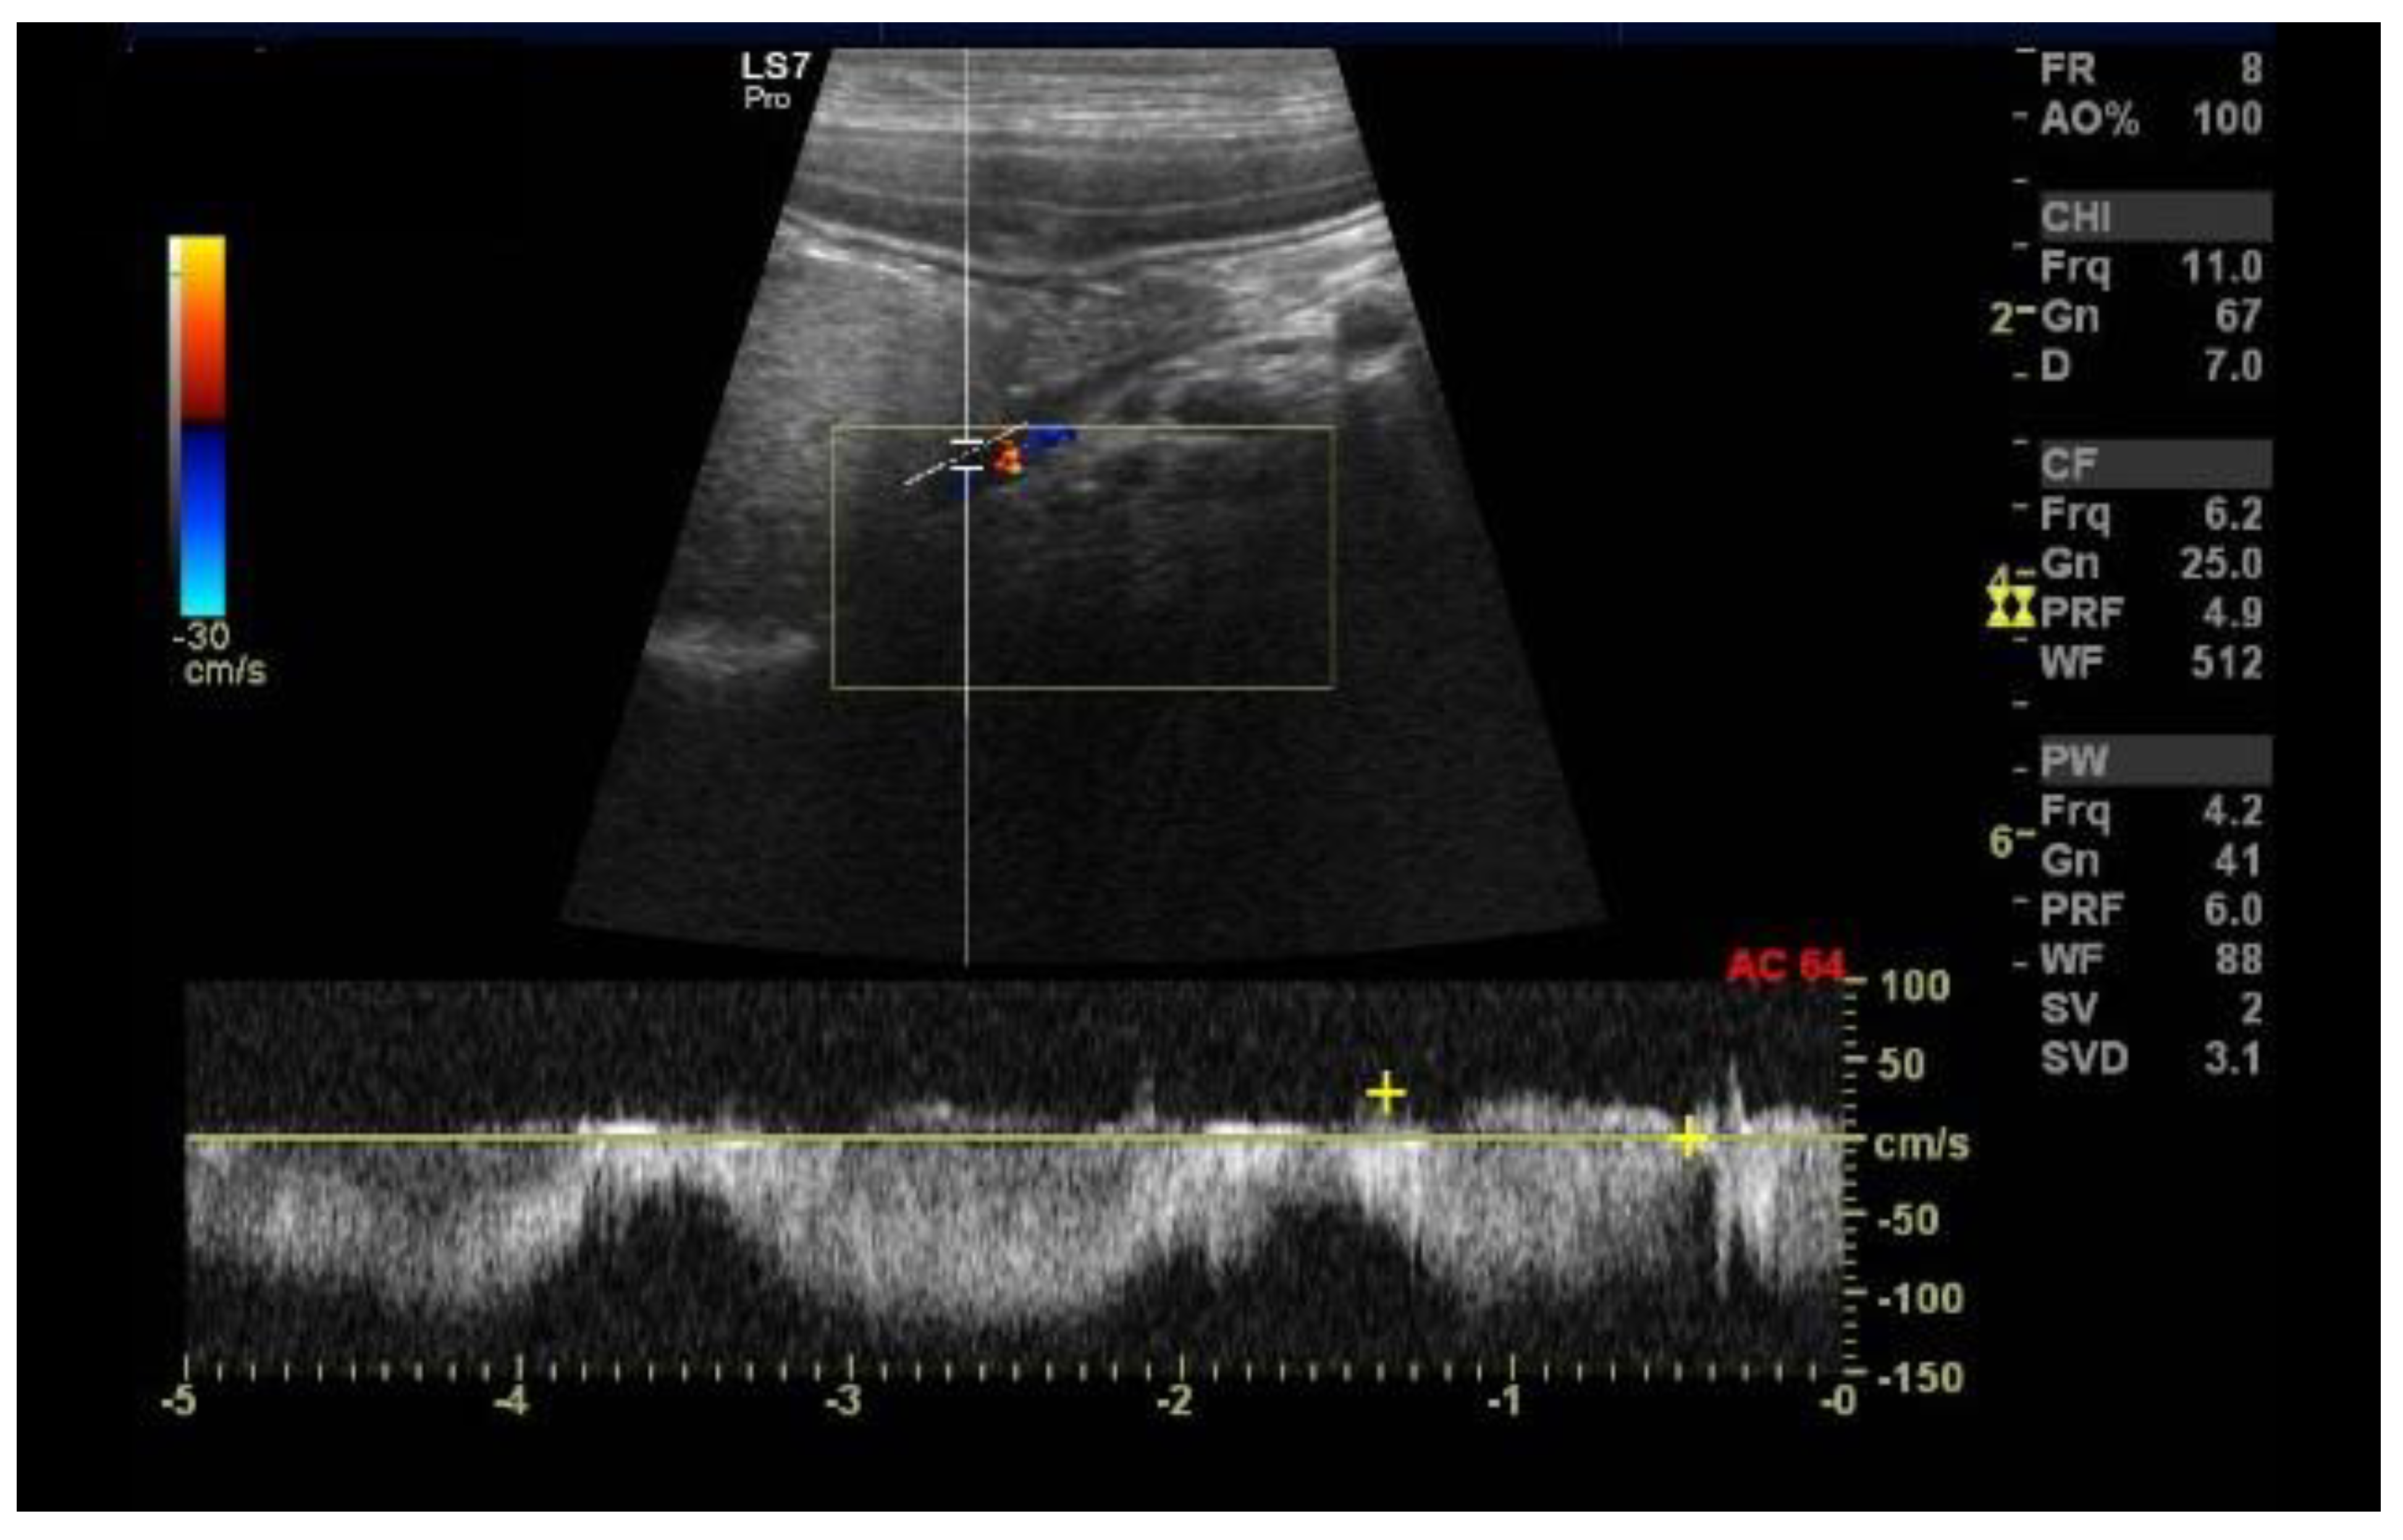

2.3. Case C (Dog)

6.5. Portal Vein Blood Flow